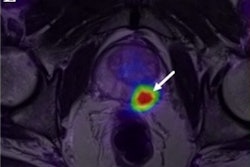

A case of peritoneal thickening not seen on CT and also showing no FDG avidity. Enhancement of pulse-contrast MRI sequences detected peritoneal carcinomatosis, which was later confirmed in surgery. Image courtesy of Dr. Felipe Furtado.Peritoneal carcinomatosis is not uncommon in gastrointestinal cancers, which account for one in three cancer deaths globally, and its detection on imaging is paramount to establish adequate patient management, Furtado said. Ultimately, this study shows that negative findings on PET/MRI can rule out peritoneal carcinomatosis with high confidence, he added.